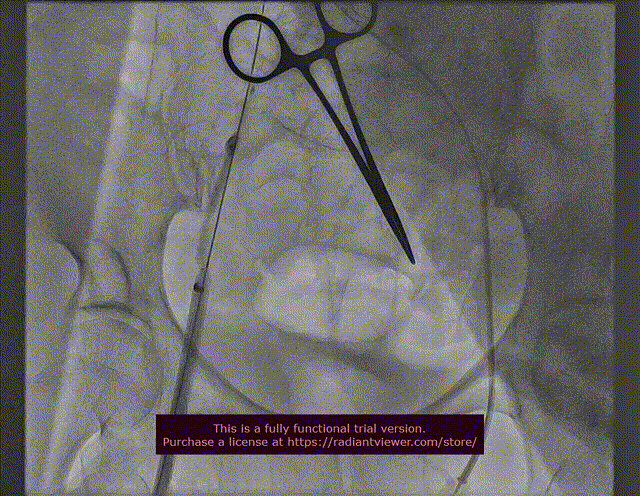

11. 造影撤出左股动脉和右股静脉鞘管

左股动脉撤出鞘管

右股静脉撤出鞘管